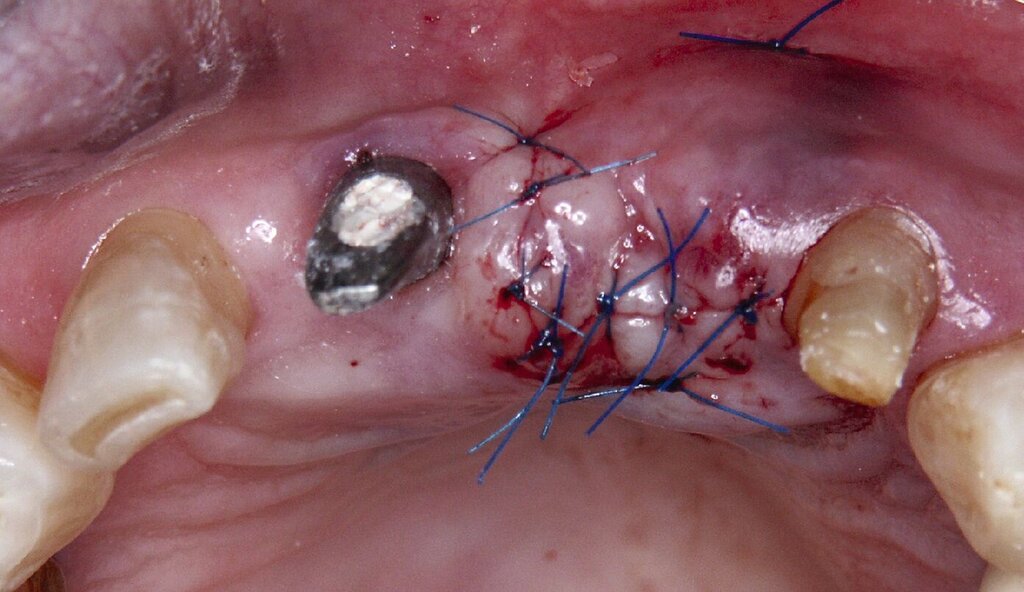

Da sechs Monate nach der Explantation keine nennenswerte knöcherne Regeneration festzustellen war, wurde eine zweizeitige Implantation nach Knochenaugmentation mithilfe dünner Knochenscheiben aus dem Kieferwinkel geplant. Die Entnahme erfolgte mit oszillierenden Instrumenten (Piezosurgery). Der Knochenblock wurde in dünne Scheiben geschnitten und mit Osteosyntheseschrauben am Alveolarfortsatz fixiert (Abb. 3e). Darüber wurden die Weichgewebe dicht vernäht. Weitere fünf Monate später erfolgte die Schraubenentfernung und die Implantation von zwei Bone-Level-Implantaten in regio 12 und 22 mit geschlossener Einheilung (Abb. 3f und 3g). Bei der Implantatfreilegung weitere sechs Monate später wurden die Weichgewebsdefizite im Brückengliedbereich durch ein kombiniertes Bindegewebs-/Schleimhauttransplantat aufgefüllt und gleichzeitig die keratinisierte periimplantäre Gingiva und Alveloarmukosa verbreitert (Abb. 3h und 3i). Die prothetische Versorgung erfolgte erst weitere drei Monate später, nach dem Konsolidieren der Weichgewebe. Die umfangreichen Augmentationsmaßnahmen konnten das transversale Weichgewebsdefizit vollständig kompensieren, während das verbleibende vertikale Defizit zu zervikal etwas längeren Kronen und Brückengliedern führte. Aufgrund der guten Abdeckung durch die Oberlippe kann das ästhetische Ergebnis als zufriedenstellend bewertet werden (Abb. 3j bis 3l).